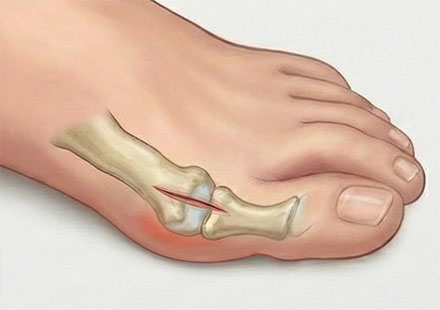

이런 증상이 있다면 '2cm 교정술'이 필요합니다!

단순 미용 목적이 아닌, 발의 기능을 회복해야 하는 신호입니다.

엄지발가락이 옆으로 심하게 휘어 둘째 발가락과 맞닿는다.

튀어나온 관절 부위가 신발을 신지 않아도 통증이 있다.

엄지발가락 쪽 힘이 빠져 자꾸 발바닥 바깥쪽으로 걷게 된다.

발바닥 앞부분에 굳은살이 있고, 통증이 있다.

교정기나 보존치료를 받아도 호전이 없다.